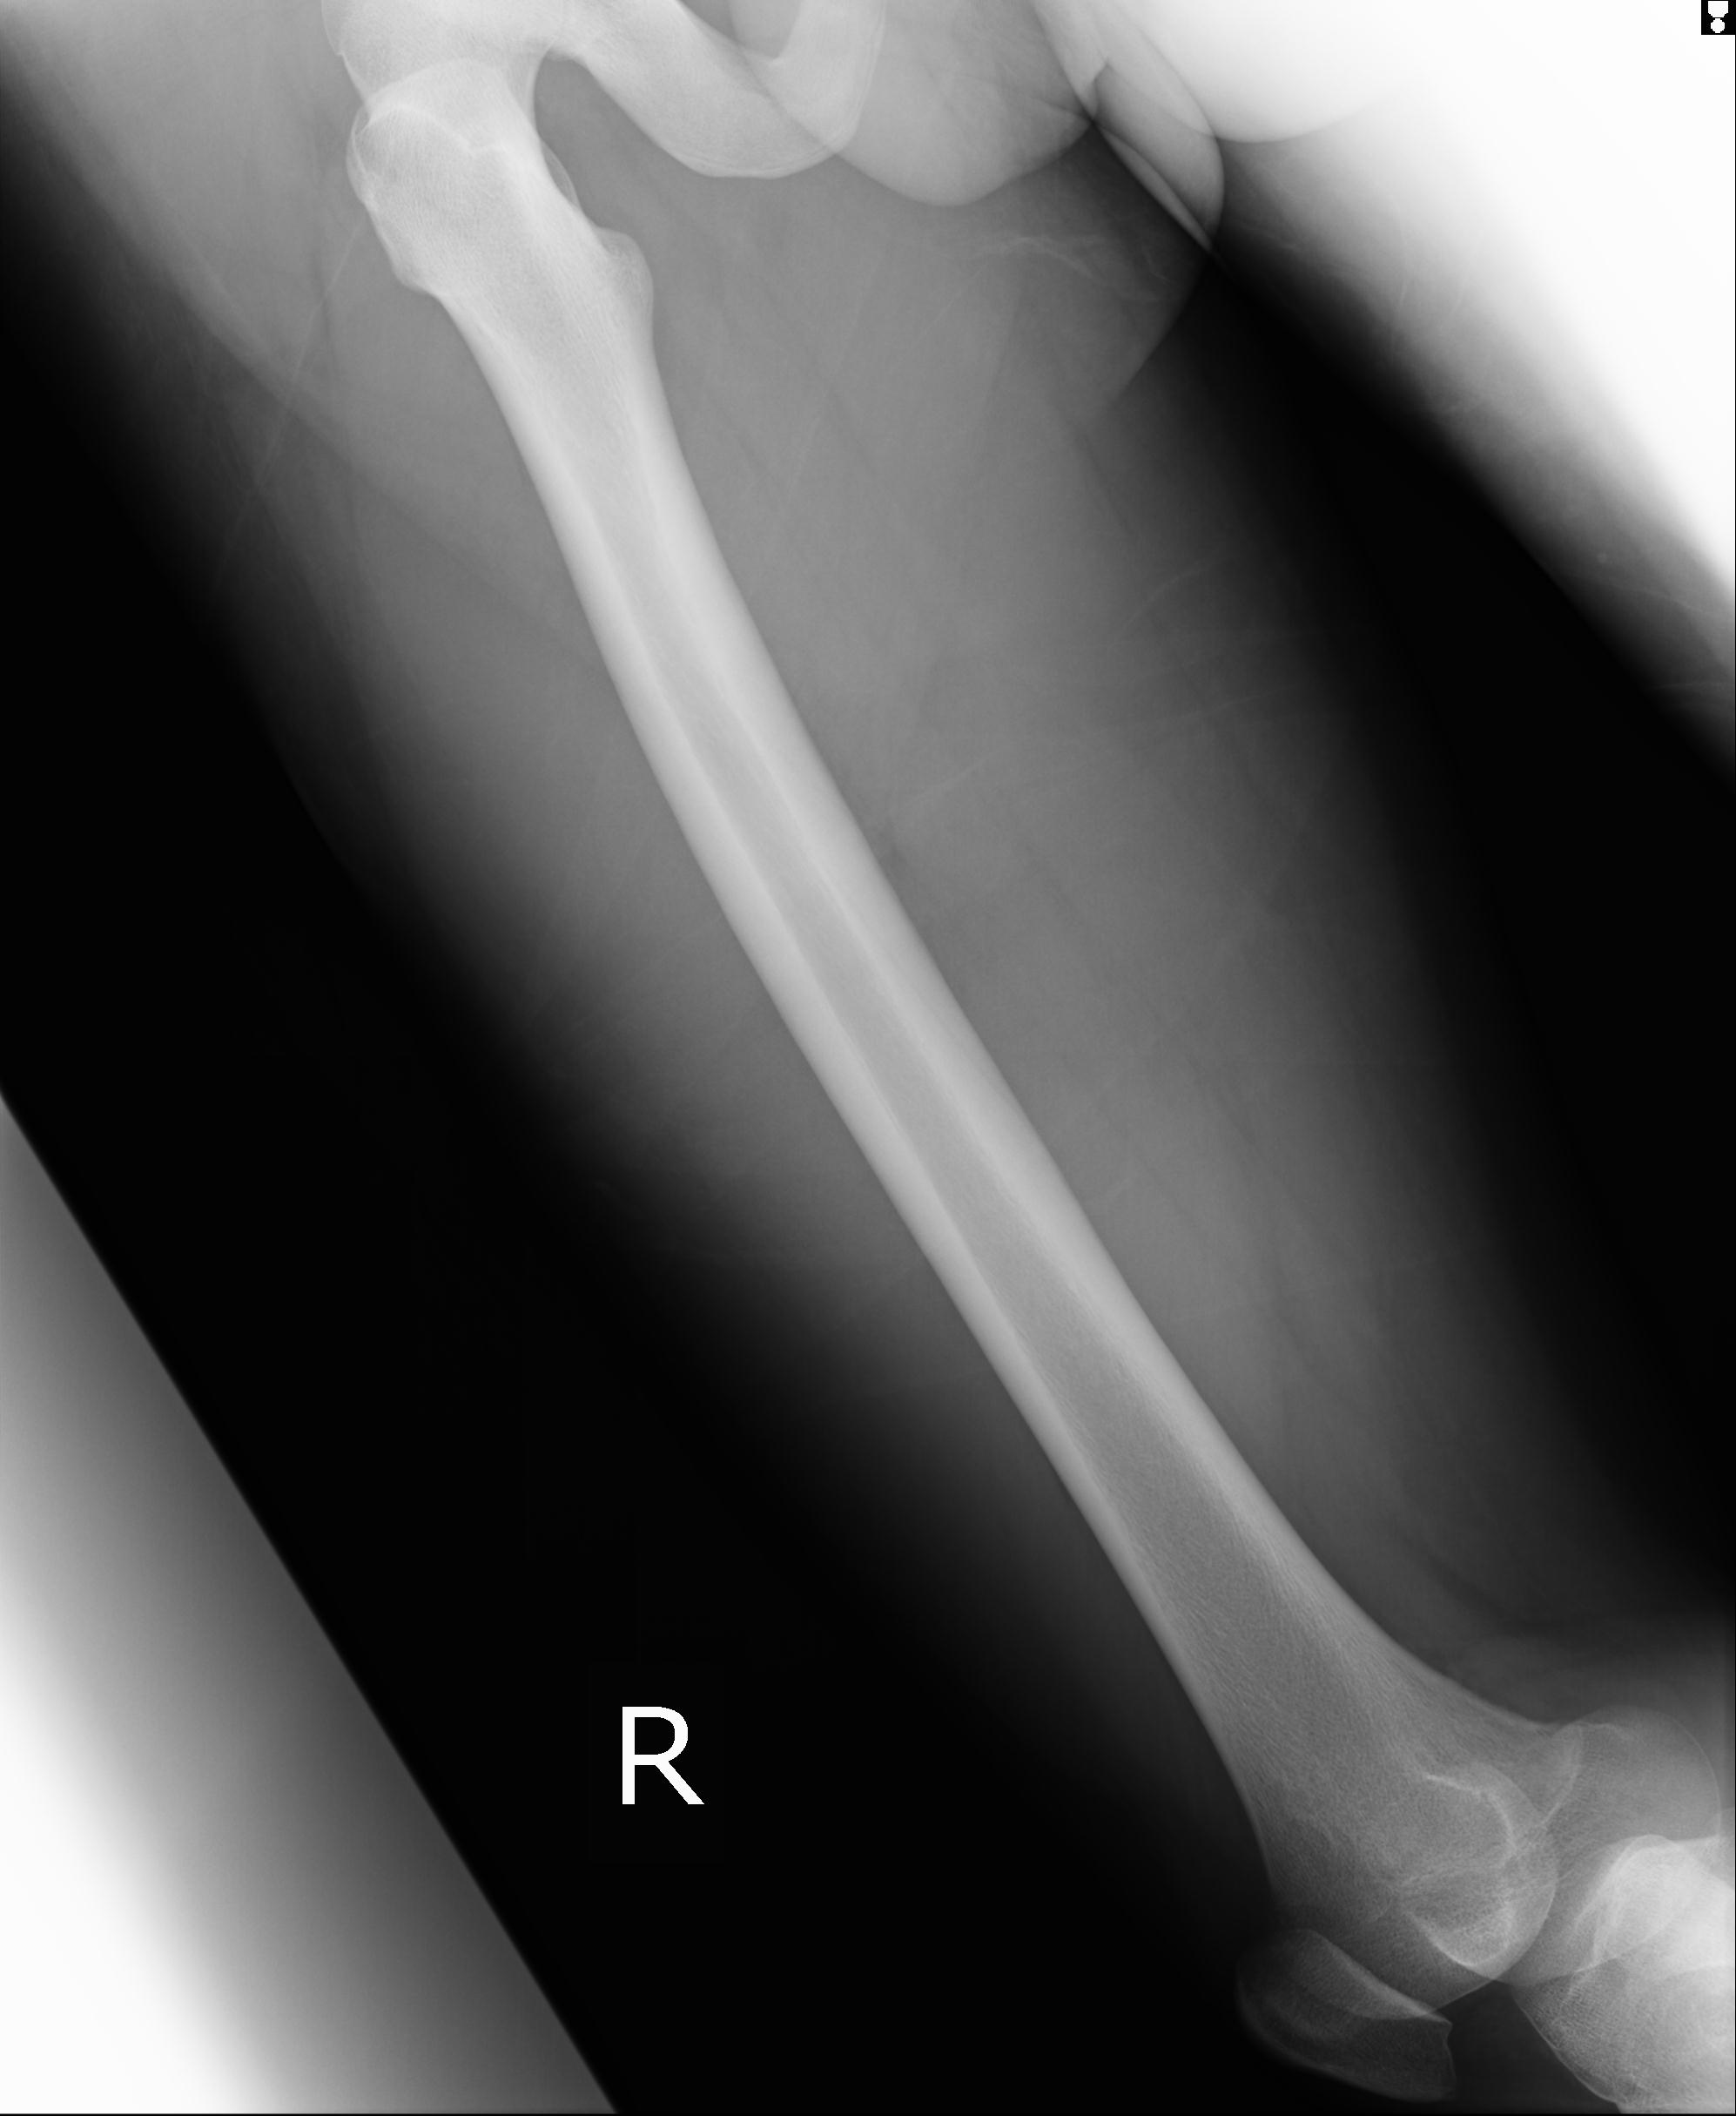

110211 1/6 1/8 左前腕 4R 15歳男性 橈骨骨幹部骨折